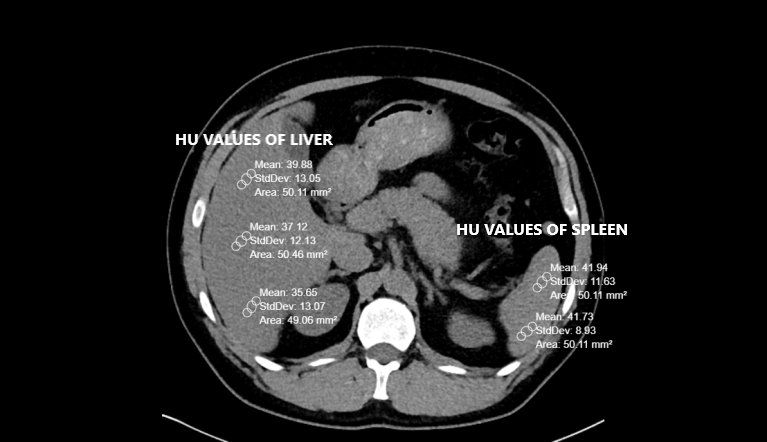

Na TC a avaliação é feita na fase pré-contraste. Avalia-se objetivamente através do valor absoluto e comparativo do ROI (diferença >5 entre fígado e baço) e subjetivamente através da visualização dos vasos.

A

Verdadeiro.